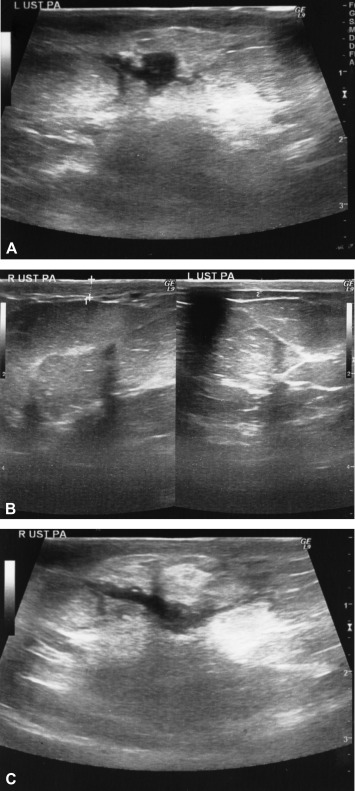

The most useful method for evaluating the radiologic appearance of IGM is sonography. The technique defines valuable data for infectious conditions such as effusions, inflammation of parenchyma and fatty tissues, abscess formations, fistula tracts. These are the key findings for discriminating the suspected lesions from malignancy. Information of the patients' history is essential to assess before evaluation. Sonography examination showed a hypoechoic collection in nine patients (90%), solid lesion in one patient (10%), thickening of the breast skin in eight patients (80%), fistula tracts in four patients (40%), and ductal fillings and postobstructive dilatation in three patients (30%). Mammographic findings were nonspecific in the three patients who underwent mammograms. Magnetic resonance imaging (MRI) evaluation may demonstrate the extension of the disease and may be used to clarify the suspected diagnosis. MRI was performed for three cases; asymmetrical enhancement with nonspecific contrast enhancement kinetics and fluid collections were common.

Common sonographic findings of IGM (A–C). (A) The most common finding is ...

Figure 2.

Common sonographic findings of IGM (A–C). (A) The most common finding is hypoechoic collections without well defined contours; (B) skin thickening secondary to inflammation should be compared with contralateral breast; right breast skin was thickened compared with the left breast; and (C) hypoechoic fistula tracts is specific finding and should be followed due to fistula formation. IGM = idiopathic granulomatous mastitis.